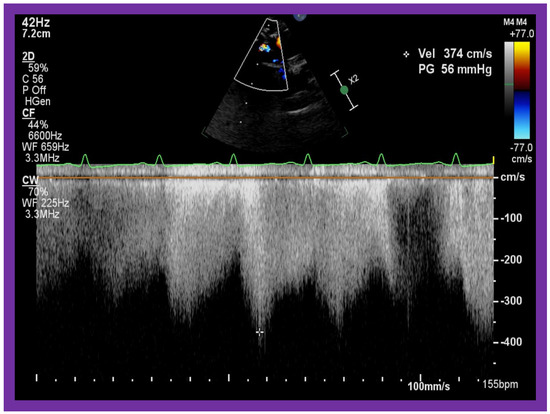

In patients who had banding of the PA, echo-Doppler studies should be scrutinized to demonstrate the banded PA diameter (Figure 22A,B and Figure 23A) and peak Doppler flow velocity across the banded PA (Figure 22C and Figure 23B); high Doppler velocity across the band (Figure 22C and Figure 23B) would suggest effective palliation. Low gradients and ineffective control of CHF may require tightening of the band; echo-Doppler evaluation is useful in making such an assessment.

Figure 22. Selected echocardiographic video frames demonstrating pulmonary artery band (PAB) with narrow diameter of 2.9 mm by 2D (A) and by color flow (B) and a high gradient (81 mmHg) by continuous wave Doppler (C) are shown.

Applsci 11 09472 g022

Figure 23. Selected echocardiographic video frames demonstrating pulmonary artery band (PAB) with narrow diameter by color flow (A) and a high gradient (88 mmHg) by continuous wave Doppler (B) are shown.